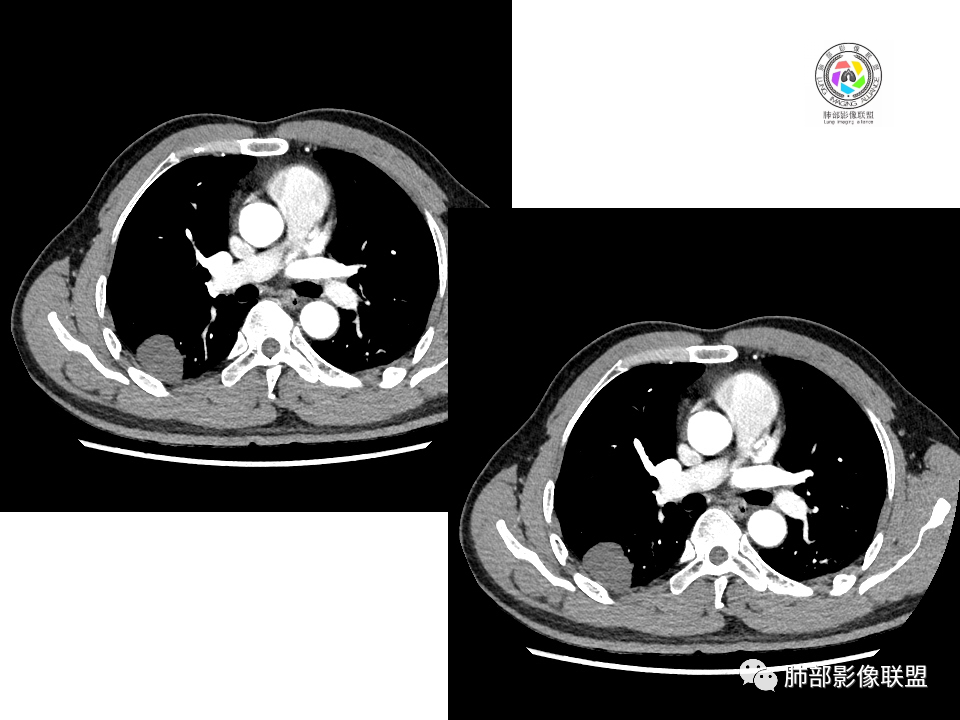

男性,49岁,体检发现,右肺下叶背段胸膜下见肿块,边界清楚,边缘光滑,胸膜下脂肪间隙存在,有分叶,无毛刺,均匀强化,内无坏死,右肺下叶血管束间不规则实性结节,边界清楚,无明显强化,中叶少许斑片状高密度影,纵隔未见明显增大淋巴结,考虑良性病变。

体检发现右肺下叶胸膜下类圆形肿块,边界清晰,有膨胀感,胸膜下脂肪间隙清晰,密度均匀,增强轻度均匀强化。另右肺下叶血管束间可见一小结节影,与胸膜下大结节类似。考虑为良性病变。

中年男性,体检发现,有吸烟史。影像见右肺多个结节、肿块影,大者位于背段,靠近胸膜下类圆形肿块,密度较均匀,边缘光滑,有膨隆,浅分叶,周围有磨玻璃影,有血管进入,似与支气管关系不大,宽基底与胸膜相连、扶墙,轻度强化;纵隔内无明显肿大淋巴结。首先考虑炎性隐球菌可能,需鉴别:肿瘤病变转移。

右肺下叶占位,胸膜下,与胸膜关系密切;

密度均匀;糊墙,边缘膨隆为主;

部分血管推移。

支气管如何?

秦化君: 似乎无关

张燕萍: 没看到堵塞哦落花时节: 没看到支气管进入南边:好,都在门口。

浅分叶

血管也是稍推移,在边缘,病灶密度均匀,边缘稍收缩;均匀强化;

这两个病灶的密度、强化、形态、边缘、与血管的关系类似;还是一元论吧。

2.右肺下叶背段胸膜下块影,边界清楚光整,上下极见磨玻璃晕,未见明显分叶毛刺和棘状突起,未见胸膜凹陷或胸壁侵入。密度均匀,轻度不均匀强化。未见支气管进入。

1.边缘光整干净,大病灶缺乏坏死等,不符合鳞癌影像学特征。尽管有吸烟史,还是偏年轻。

2.边缘光整,会是小细胞癌或是大细胞癌吗?小细胞癌的肺门纵隔淋巴结增大往往十分夸张,该患者不符合。